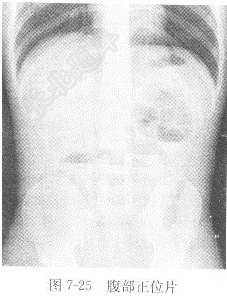

试题详情单项选择题男性,25岁,阵发性腹痛、腹胀2天,腹部平片见图7-25,X线诊断为( )。 A、消化道穿孔B、正常腹部平片C、结肠梗阻D、小肠梗阻正确答案:关注下方微信公众号,搜题查看答案热门试题亚急性期血肿心肌梗死出现的ST段抬高应与哪些疾病鉴别消化道穿孔题见图6-12。心脏大正常心电图检查泌尿系结石活化部分凝血活酶时间(AFTT)雌激素受体(ER)与孕激素受体(PR)肾结石题见图6-15。血液酸碱度(pH)尿hCG检测左右束枝传导阻滞检查肺内占位病变心肌缺血与心肌梗死脾外伤血清氨基转移酶血浆凝血酶原时间(PT)上(下)消化道造影